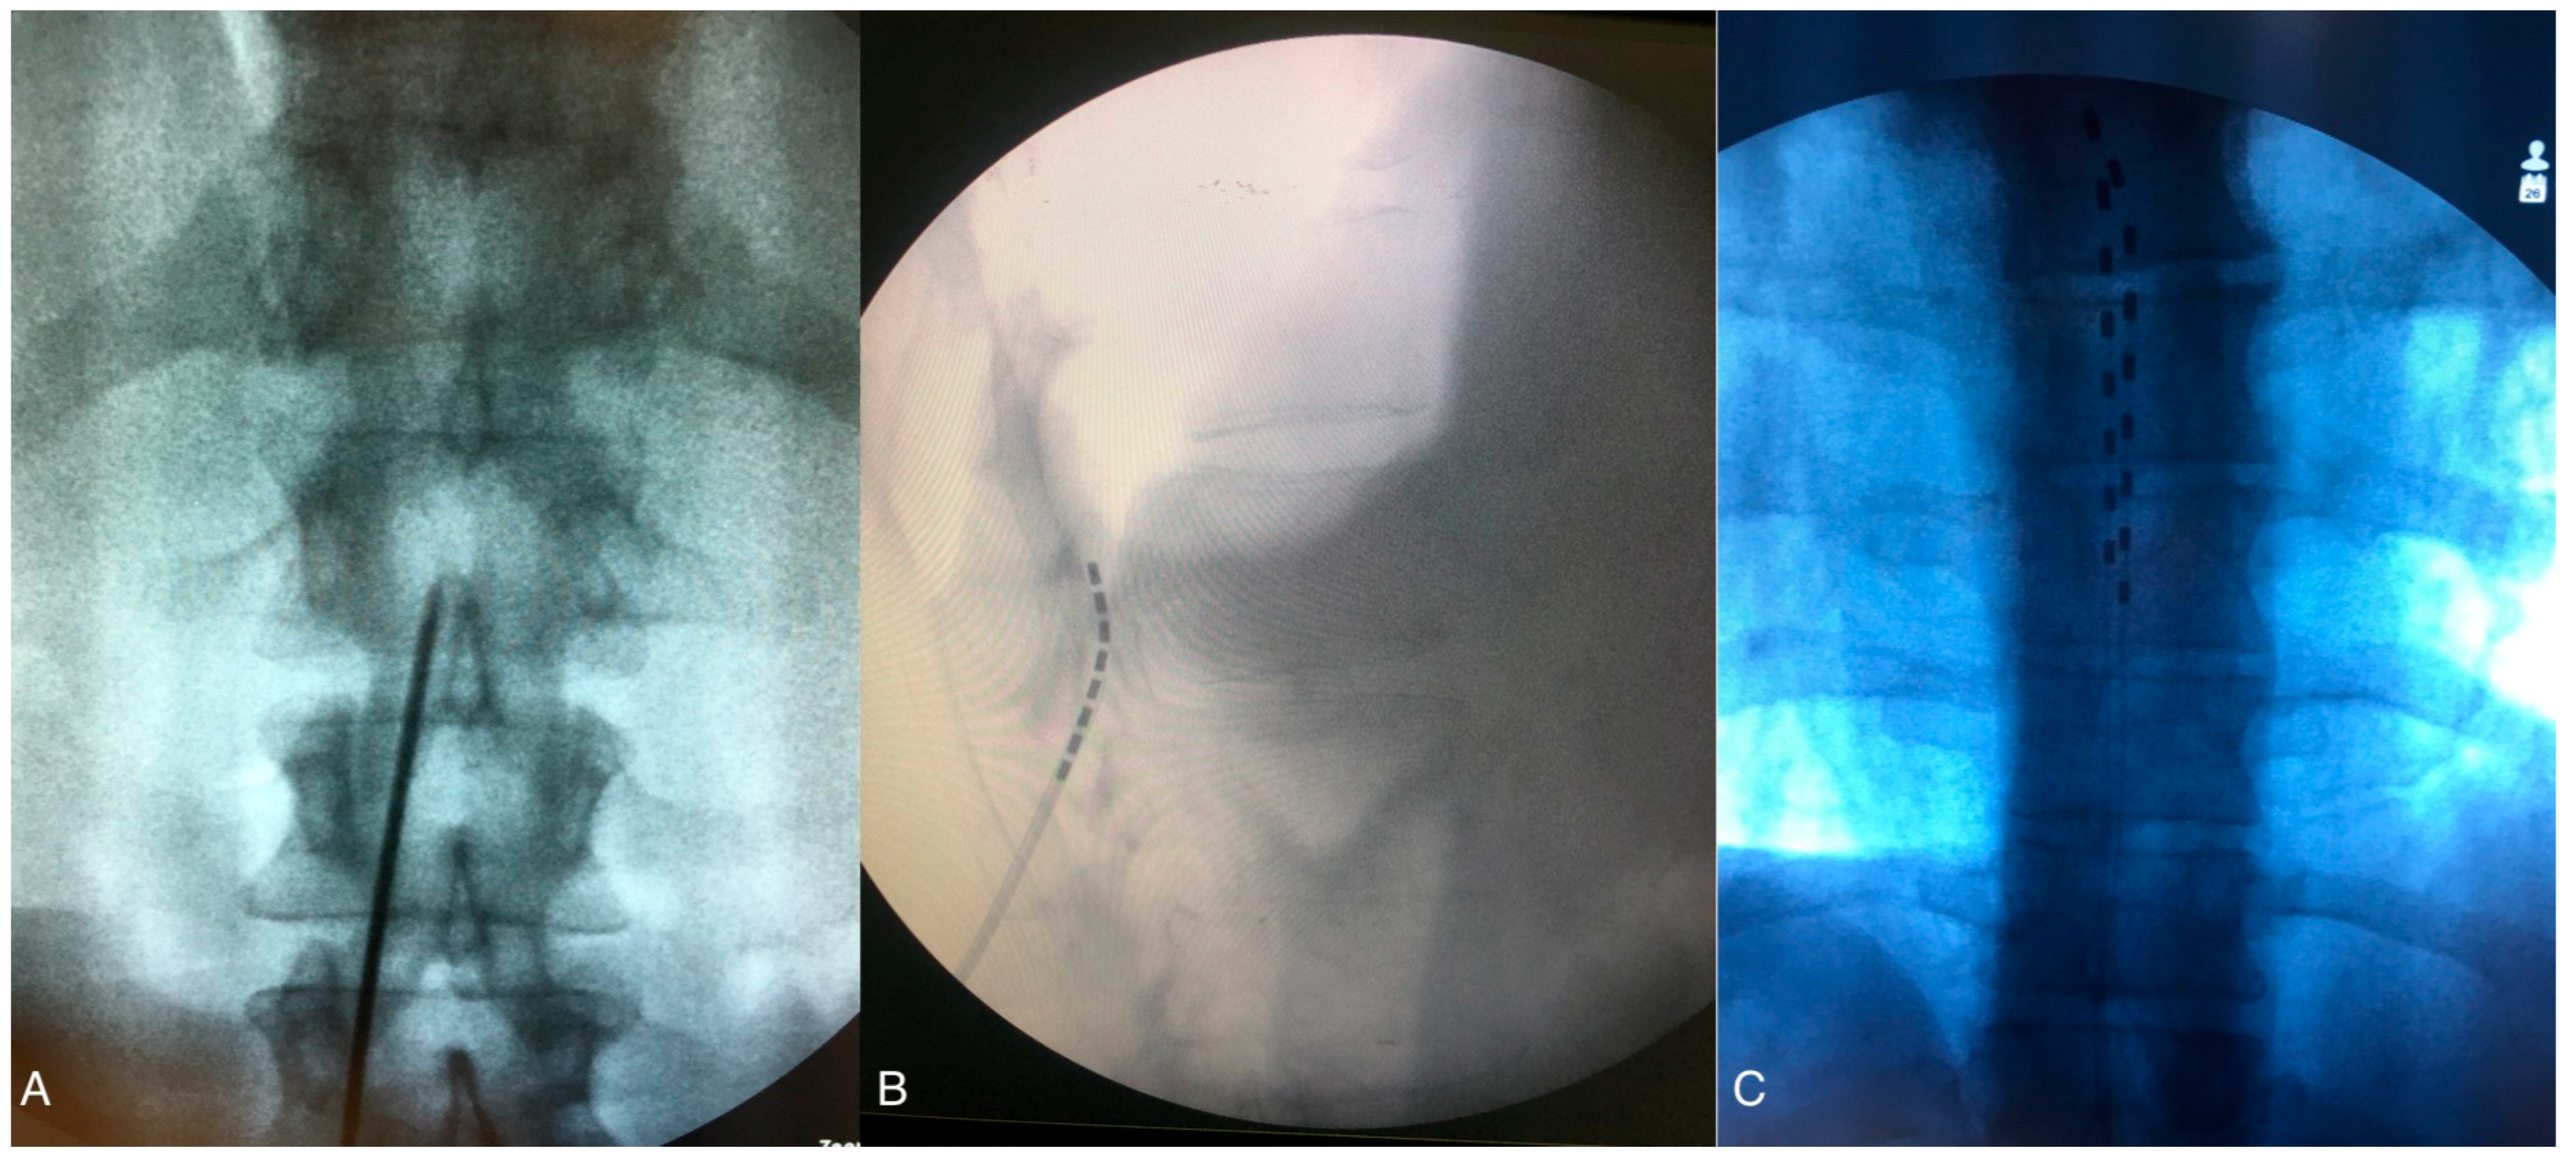

2.2. SCS Surgical